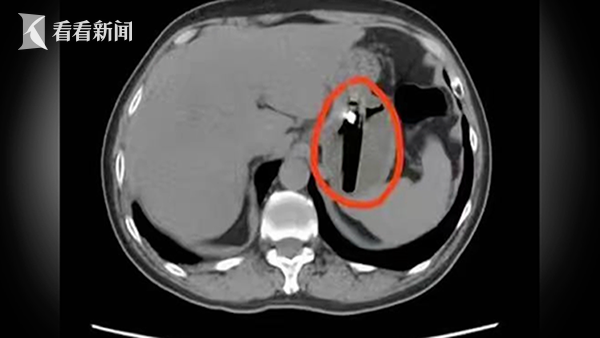

近日,武汉市民陈先生腹部疼痛难忍,长达一个月,以为是老胃病复发,但吃护胃药也不见好,到医院就诊检查才发现胃中竟藏有一个打火机。

据悉,这枚塑料打火机长约8厘米,在陈先生的胃中反复摩擦,引发巨大溃疡,而胃酸持续腐蚀,可能会导致打火机外壳破损,内部可燃气体泄漏会引发中毒,重则爆炸、胃穿孔,甚至危及生命。为避免手术导致打火机二次损伤,医生团队创新采用医用防护套,将打火机完整包裹后取出,术后陈先生回想起一个月前与朋友聚餐宿醉的经历,怀疑是当时误吞了打火机。